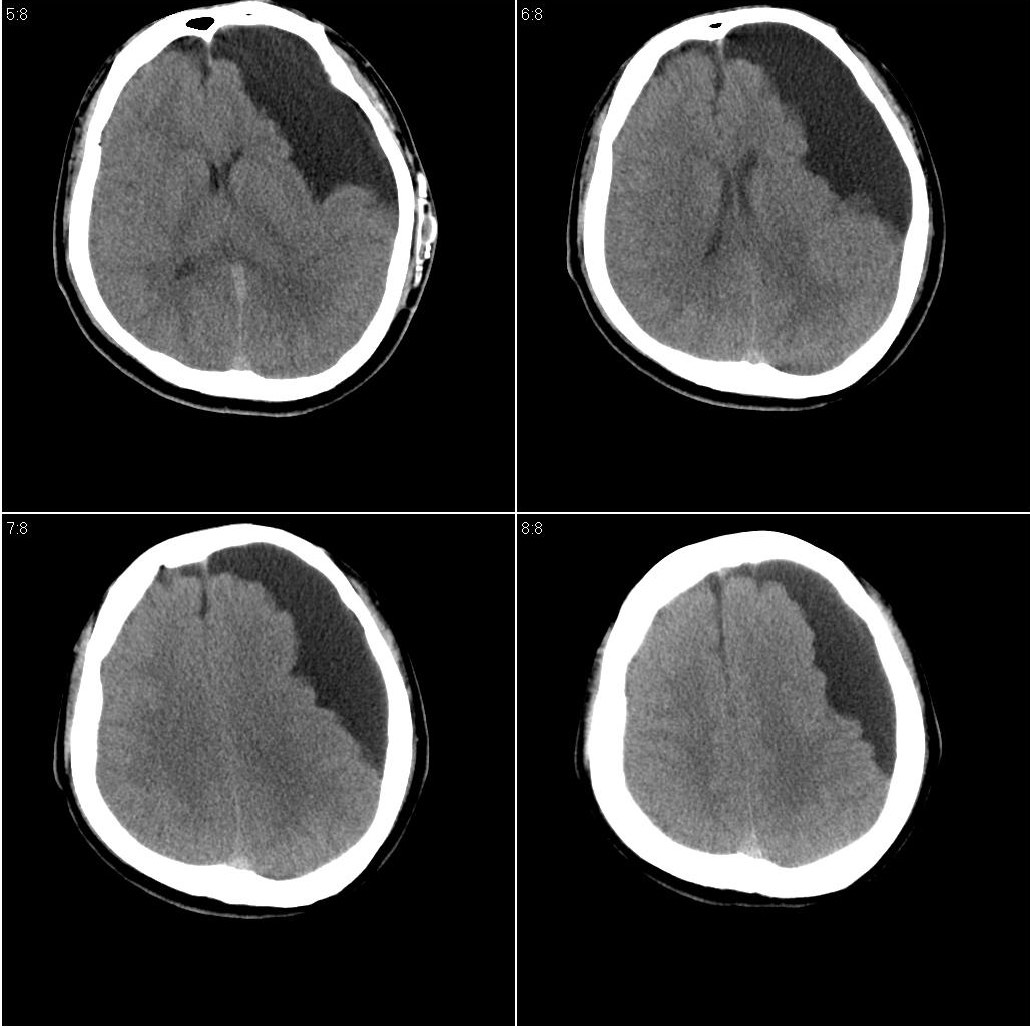

以下是引用随光逐影在2009-8-1 17:07:00的发言:[br]左侧中颅窝及左侧额颞顶部蛛网膜囊肿,并囊液引流术后。

以下是引用hhcckk在2009-8-1 17:29:00的发言:[br]左侧额颞部囊状低密度影,边缘平直,有明显占位效应,考虑蛛网膜囊肿,病变导致左额颞部受压,精神症状可与此有关,李松年编的ct诊断学上有过介绍,额叶联合区损害可引起智力、性格、精神症状,也就是9、10、11区[br][br]